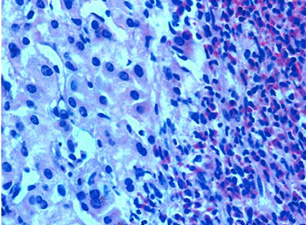

При повторном исследовании кала яйца гельминтов найти не удалось. Пациенту была выполнена биопсия печени, при исследовании биоптатов был заподозрен диагноз стронгилоидоза. Однако впоследствии он был исключён, и при повторном изучении материалов биопсии выявлено массивное пропитывание ткани печени эозинофилами (рис. 1). Особенно много эозинофилов было вокруг жёлчных протоков различного калибра, в меньшей степени — по периферии сосудов, стенки которых были утолщены за счёт пролиферации (рис. 2).

Рис. 1. Массивное пропитывание ткани печени эозинофилами как показатель паразитарной природы заболевания

Рис. 2. Окраска гематоксилином и эозином биоптата печени, увеличение ×400. Массивное скопление эозинофилов вокруг жёлчных протоков